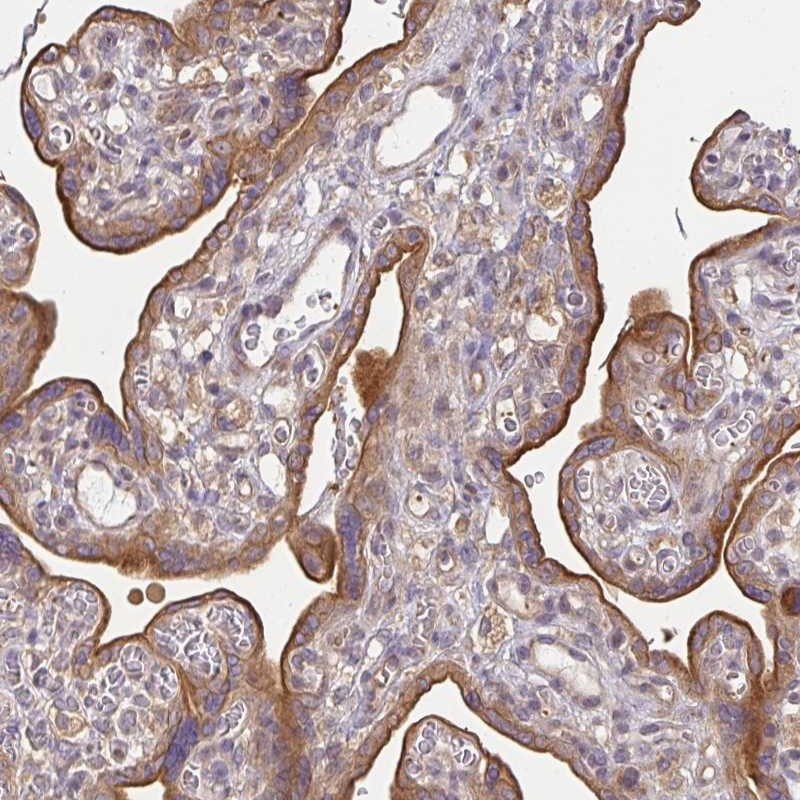

Immunohistochemical staining of human placenta shows moderate cytoplasmic and membranous positivity in trophoblastic cells.